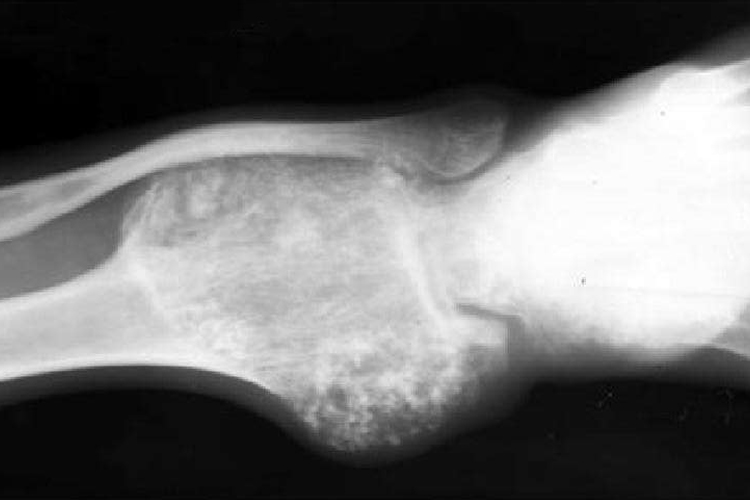

骨肉瘤:骨肉瘤患者X光可表现为不同形态,密质骨和髓腔有成骨性、溶骨性和混合性骨质破坏,骨膜反应明显,呈侵袭性发展,可见Codman三角或呈日光射线形态。

软骨肉瘤:此类患者X光常表现为千骺端的髓腔内有一单房或多房性骨密度降低或透亮区,边界不规则,其内可见斑点状或块状的钙化,部分病人肿瘤穿破新生骨形成袖口征。

骨膜肉瘤:对于骨膜肉瘤患者,骨旁可有瘤体形成,早期瘤体与骨的分界线清楚,其间可见一条透亮区,随着病变的发展,瘤体可浸润骨质,骨质破坏。瘤体常呈分叶状、圆形,瘤体内有许多新骨形成,并伴随骨小梁出现。